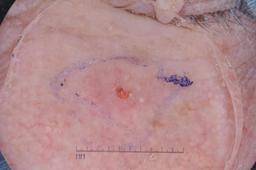

ISIC-DICM-17K (ISIC Dermoscopic Images and Clinical Metadata 17K) is a curated and balanced dataset derived from the International Skin Imaging Collaboration (ISIC) Archive Gallery. It comprises 17,060 dermoscopic images and clinical metadata (8,530 melanoma and 8,530 non-melanoma classes).

For more details, please follow the project’s GitHub repository: https://github.com/mmu-dermatology-research/isic-dicm-17k

This dataset was used in this study and benchmark to explore the effectiveness of multimodal learning for skin lesion classification:

S. Ahammed, X. Cui, W. Lu and M. H. Yap, "Skin Lesion Classification using Dermoscopic Images and Clinical Metadata: Insights from Multimodal Models," 2025 IEEE/CVF Conference on Computer Vision and Pattern Recognition Workshops (CVPRW), Nashville, TN, USA, 2025, pp. 222-230, DOI: 10.1109/CVPRW67362.2025.00027